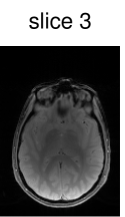

To verify the in-vivo applicability, human brain images of a healthy volunteer were acquired using the above described GRE sequence modified to include the optimized CAIPIRINHA-based pulses. The sequence parameters were set to , , bandwidth , matrix size and FOV . After acquisition, the k-space data of the individual slices were separated using an offline slice-GRAPPA ( coils, kernel size of ) reconstruction [42, 9]. The reference scans used in the slice-GRAPPA reconstruction were performed with the same sequence using an optimized single-slice pulse (not shown here). To decrease the scanning time, we acquired k-space lines ( of the full dataset) around the k-space center for each reference scan. After this separation, a conventional Cartesian reconstruction was performed individually for each slice.

Figure 6 shows the image reconstruction using optimized RF pulses for simultaneous excitation of two, four and six slices with the same slice separation and thickness as above. As can be seen clearly in the first column, all three pulses lead to the desired excitation pattern in-vivo as well. The remaining columns show the slice-GRAPPA reconstructions, which illustrate that the excitation is uniform across the field of view.